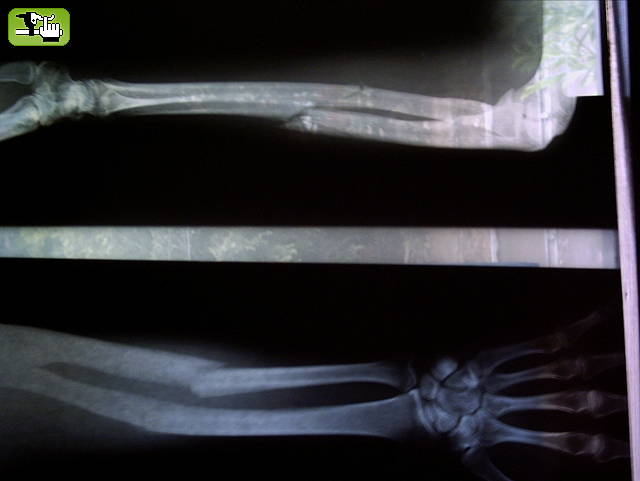

Me volvi a partir un hueso....esta vez fue doble... quedo a 90 grados!!!! el brazo!!!

..por suerte esto fue hace dos meses y medio...y ya llevo 15 dias de rehabilitacion... en dos semanas mas vuelvoooo!!!